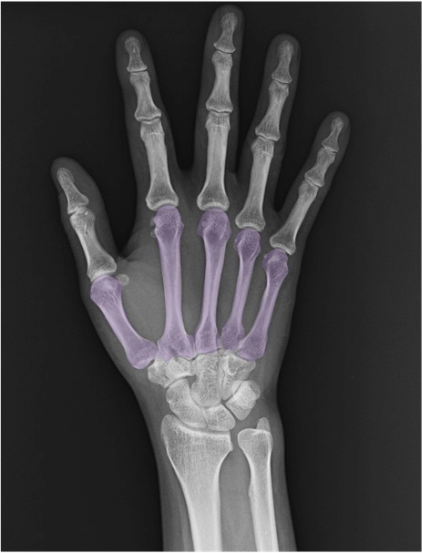

中手骨・指骨

中手骨(metacarpal (bone))

第1〜第5の5本。PA像では基部(base)〜骨幹(shaft)〜骨頭(head)の連続性、骨皮質の途切れや骨梁配列をチェック。第1中手骨は短く、母指球側へ配列。

基節骨(proximal phalanx)

全指に存在。PA像で基底部の関節面とMCPとの整合、側面像で骨皮質の途切れ(裂離骨折など)に注意。

中節骨(middle phalanx)

第2~5指に存在(母指は欠如)。PIPとDIPのランドマークとして基部・頭部の形状を把握。

末節骨(distal phalanx)

末端の爪下骨。PA像で末節骨末端の“tuft(末節骨末節部)”の形態評価、打撲後は骨折線や爪床下血腫の示唆所見に注意。